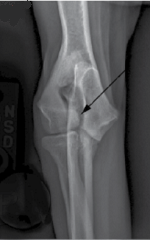

Radiographs (x-rays) are the first line of diagnosis of either IOHC prior to a fracture or the actual fracture itself. X-rays of IOHC before an actual fracture can be hit-or-miss. The fissure line would show up on x-rays as a thin black line, called a radiolucent line extending through the condyle. In the x-ray image at the right here, the black arrow points to a radiolucent line across the humerus condyle, indicating IOHC. [Image is courtesy of Dr. Felix Michael Duerr, Canine Lameness (2020) Fig. 14.4(A)]